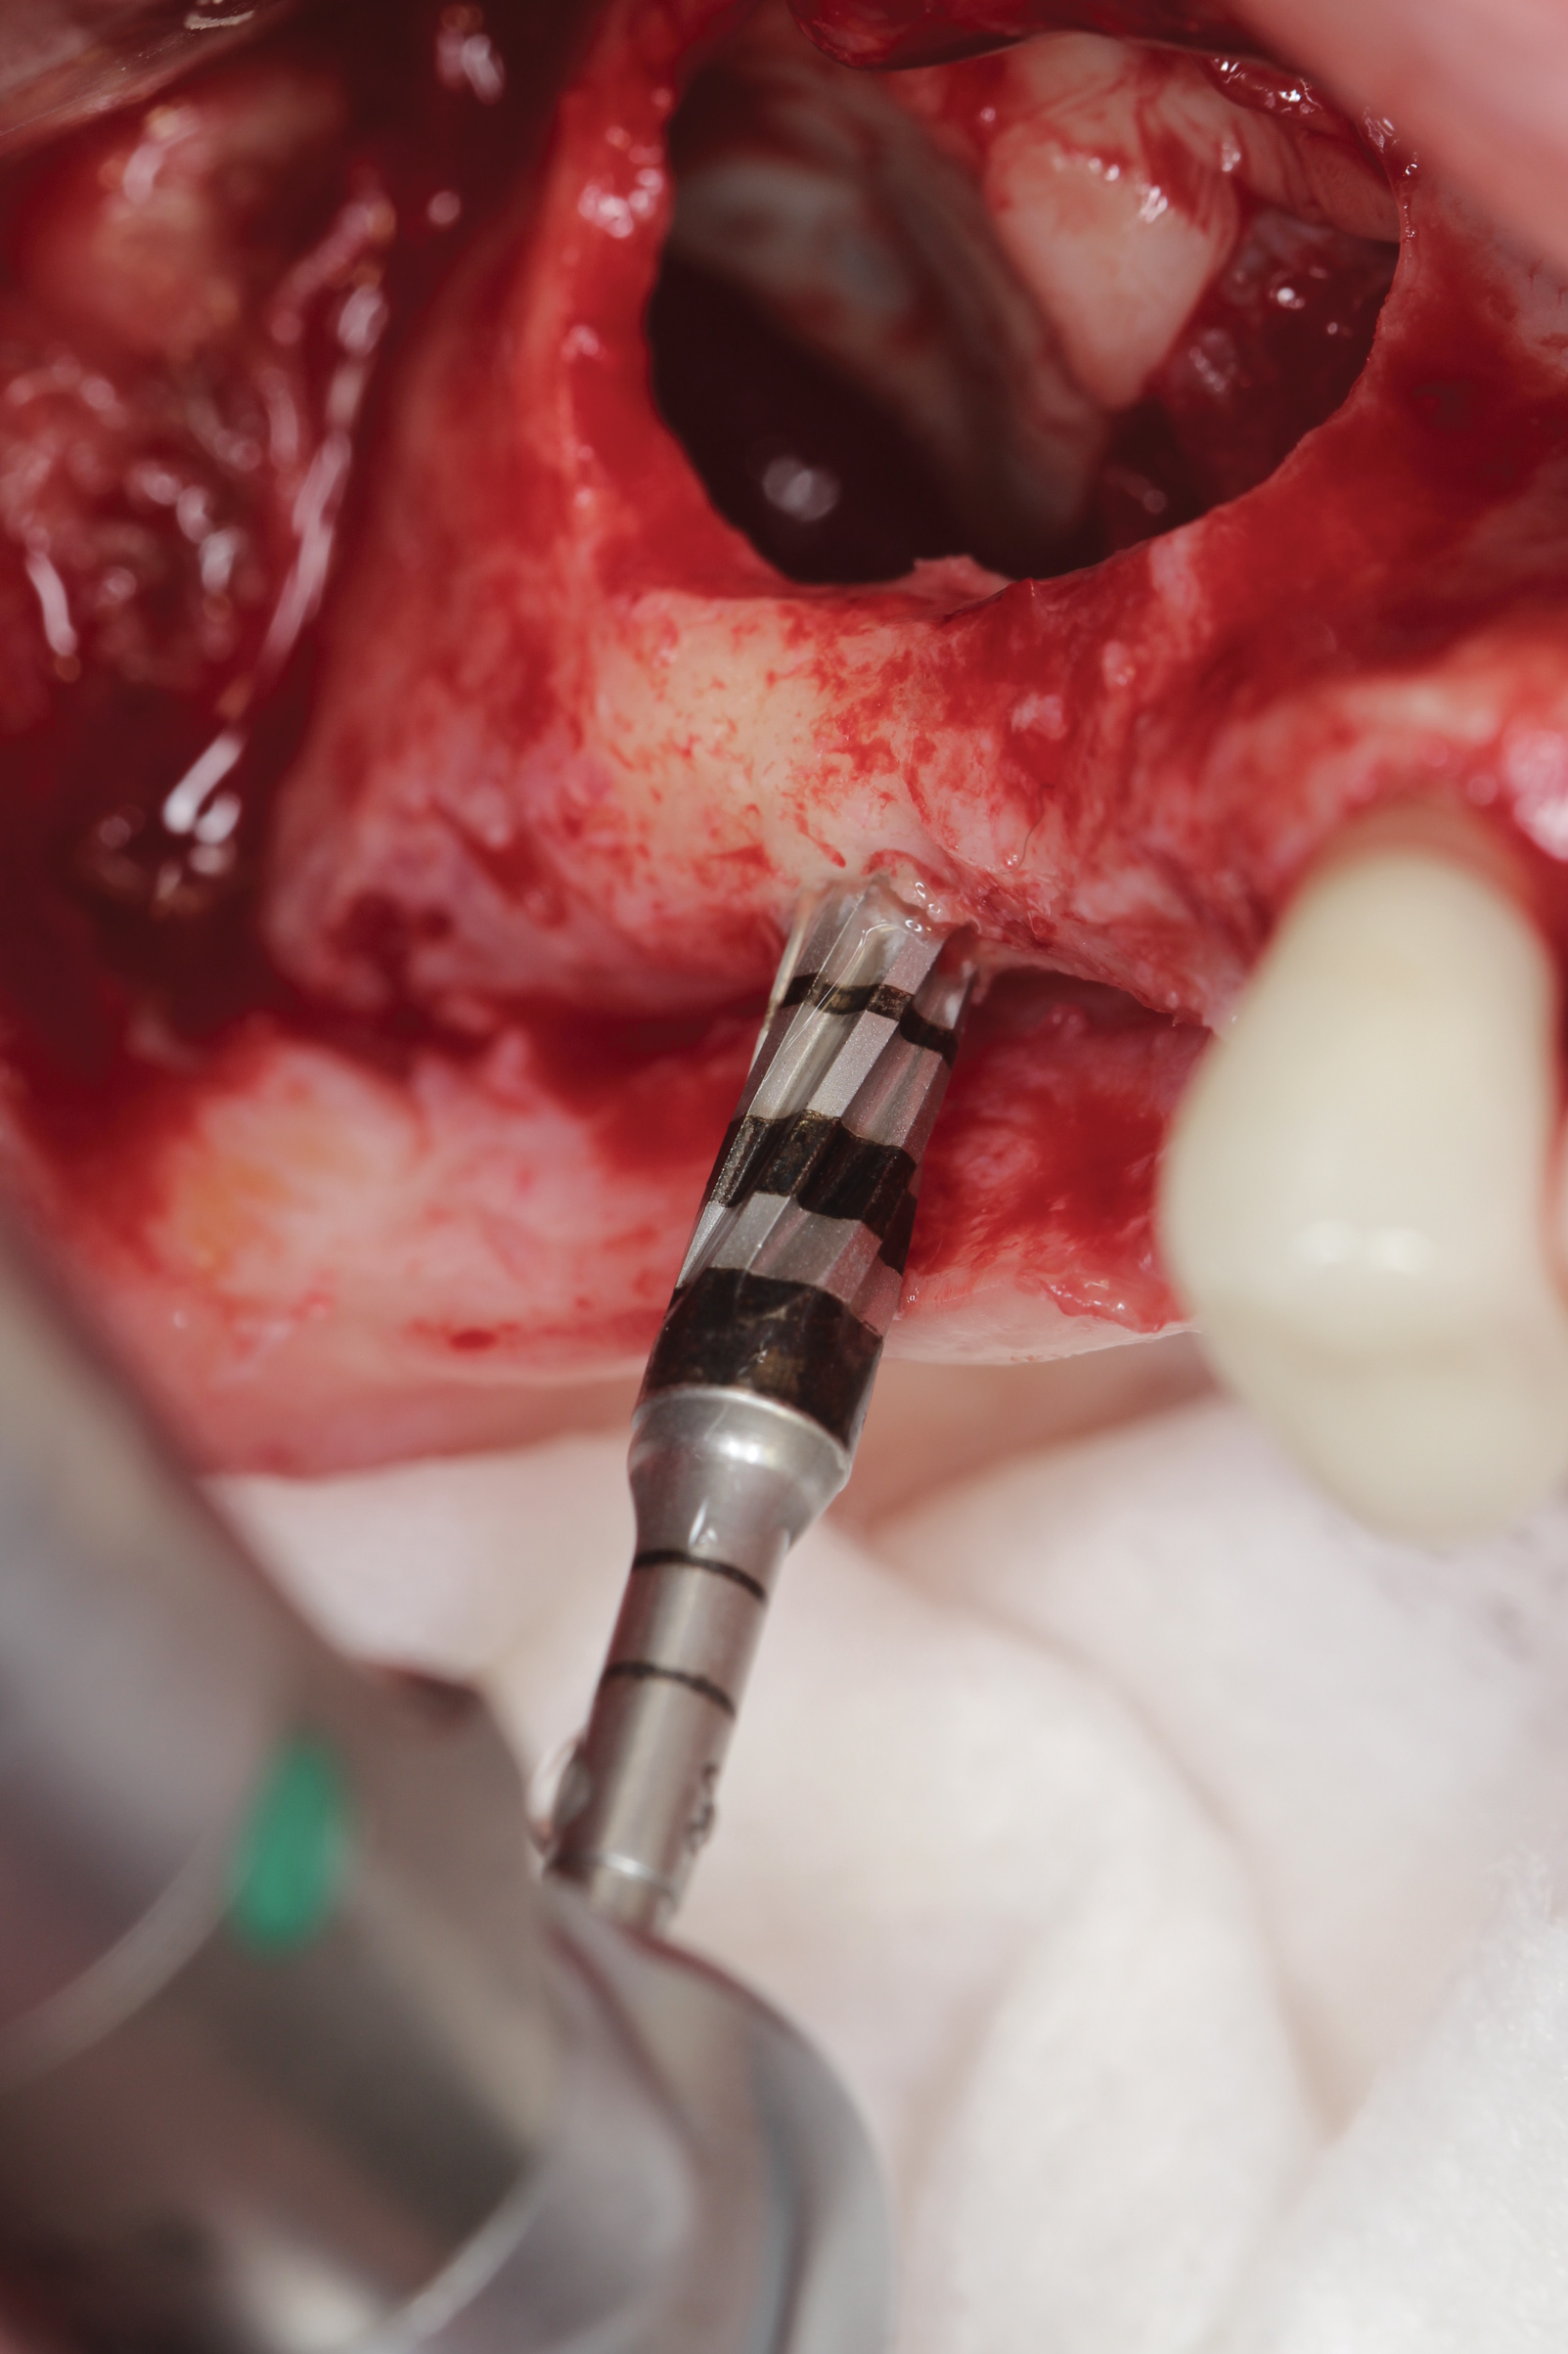

Appropriate rotary burs were used to section the tooth in half in the mesial-distal direction, followed by careful removal of the palatal root half (Figure 17). Next, the remaining labial root was contoured to a thickness of approximately 1.5 mm followed  by removal of the apical third (Figure 18). OD burs were then utilized to densify the bone in the osteotomy via lateral bone displacement (Figure 19). A bone grafting putty (Novabone) was placed into the osteotomy and the implant was then inserted with a primary implant stability reading of 60 Ncm (Figure 20). Typically, mineralized allograft is the preferred choice for grafting between the implant body and facial root.

Fig 19. OD burs were used to create implant osteotomy.

Figure 19